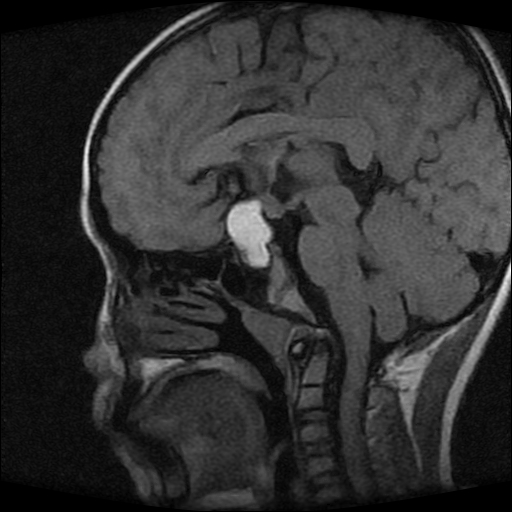

男性,12岁。反复头痛呕吐半月。脑积液无异常。病变部位ct值32hu,dwi无异常。

鞍上为主,累及鞍内,垂体受压位于鞍底。mri呈短t1、长t2信号,不太支持生殖细胞肿瘤,首考颅咽管瘤。

鞍内囊性占位性病变,t1wi、t2wi,均为高信号影。ct平扫为等密度。发病年龄较小。故首先考虑颅咽管瘤,可以做ct增强扫描